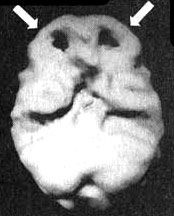

Мозг Боба - СДВ

Трехмерное изображение нижней поверхности.

Мозг в состоянии покоя - хороший уровень активности префронтальной коры (см. стрелки).